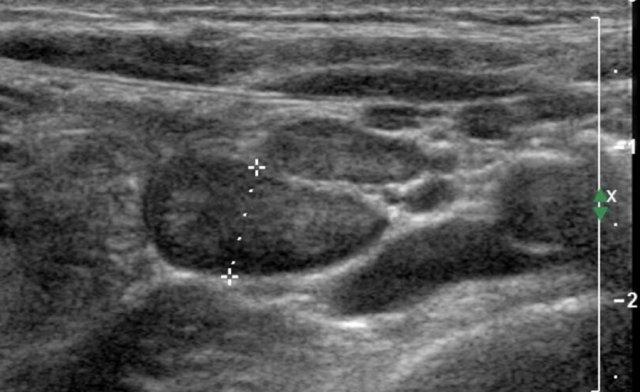

Tinh hoàn

Vật liệu và Phương pháp

Các số đo siêu âm được thu thập từ 344 bé trai thuộc nhiều dân tộc khác nhau.

Không ghi nhận sự khác biệt có ý nghĩa thống kê giữa các dân tộc hoặc giữa tinh hoàn phải và trái.

Thể tích tinh hoàn được tính theo công thức:

Chiều dài × Chiều rộng × Chiều cao × 0,523